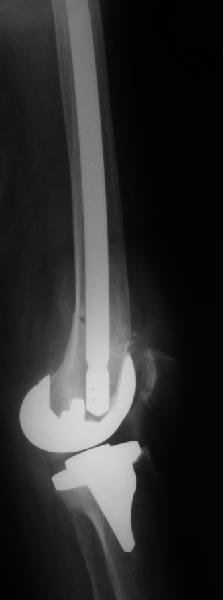

Поступила больная с перипротезным переломом

Перипротезный перелом у пациентки 67 лет . Эндопротезирование год назад . Сопутствующие нарушения ритма сердца и вес 120 кг при росте 185 .Думаю о мыщелковой пластинке с угловой стабильностью рыбинского исполнения остальное больной не потянуть . Заранее всем спасибо !